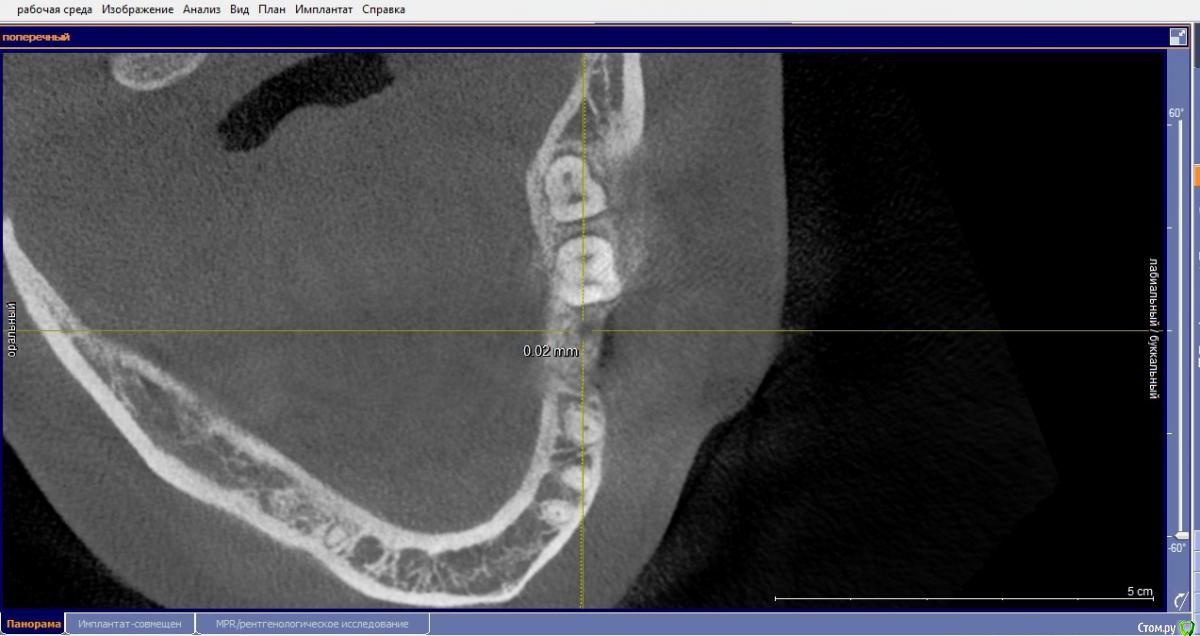

Маргарита19 Опубликовано 22 августа, 2016 Автор Поделиться Опубликовано 22 августа, 2016 Уважаемые стоматологи, помогите, пожалуйста определиться с выбором импланта и схемы лечения. вопрос идет только о 46 зубе, на синус-лифтинг пока не могу решиться. Посетив несколько клиник, стою перед выбором из 2 вариантов: 1. Имплант Нобель Коникал коннекшн (8 мм), временные коронки, потом циркониевые коронки. Но здесь есть еще нюанс, ортодонт советует установить брекеты на нижнюю челюсть, чтобы выровнять передние зубы, там есть небольшая скученность. Сначала подпилить зубы немного по ширине, а потом приклеить брекеты только на 8 зубов, т.к. клыки смыкаются четко. Пока ТРГ и слепков нет, это предварительный план. Меня никогда не беспокоили нижние зубы в плане кривизны. Но, как я поняла, есть нездоровая стираемость зубов. 2. Хирургический шаблон, подсыпать кость искусственную, и Имплант Биотек Коннект (12мм), потом коронки МК, без временных. Про истираемость зубов ничего не сказали, но я и не спрашивала, если честно. Знакомых или проверенных врачей или клиник нет у меня. Вот пытаюсь понять в чьи руки отдаться. Ибо через пол годика хочу решиться на синус и делать его уже имея опыт общения с докторами. Какая схема на ваш взгляд более логичная и какой имлант лучше поставить? Заранее благодарю. Снимки прикрепляю как смогла сделать с КТ. Ссылка на комментарий

Bier Опубликовано 22 августа, 2016 Поделиться Опубликовано 22 августа, 2016 я бы поставил имплантат длиной 8-10мм + подсадка слизистой. По поводу брекетов - имплантата они в данном случае не касаются, это отдельная проблема. 1 Ссылка на комментарий

Маргарита19 Опубликовано 22 августа, 2016 Автор Поделиться Опубликовано 22 августа, 2016 я бы поставил имплантат длиной 8-10мм + подсадка слизистой. По поводу брекетов - имплантата они в данном случае не касаются, это отдельная проблема.Спасибо! А почему не 12?, чтобы не подсыпать кость? Ссылка на комментарий

Bier Опубликовано 23 августа, 2016 Поделиться Опубликовано 23 августа, 2016 Нет, просто в этом нет никакого смысла 1 Ссылка на комментарий

Маргарита19 Опубликовано 23 августа, 2016 Автор Поделиться Опубликовано 23 августа, 2016 Нет, просто в этом нет никакого смыслаИзвините, нет смысла в длинном импланте или в дополнит кости? Ссылка на комментарий

Доктор Хаус Опубликовано 23 августа, 2016 Поделиться Опубликовано 23 августа, 2016 Нету смысла в длинном имплантате 8-10 мм отлично передают жевательную нагрузку в кость . А вот в толстой десне окружающей место соединение имплантат абатмент есть . Чем десна толще тем будет лутще . http://s61.radikal.ru/i174/1608/36/ac44455ad8ae.jpg Даже если не хватает чуть чуть кости , то её отсутствие можно компенсировать подсадкой Десны . Это сейчас очень модно. Надежно . И для вас это будет легче. Вот примерно так..http://s012.radikal.ru/i319/1608/5e/86488fd41c8e.png Ссылка на комментарий